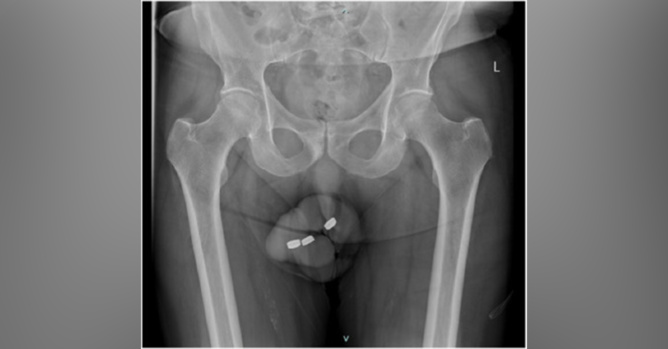

À l'âge de 73 ans, un homme s'est retrouvé dans une situation critique après avoir inséré trois piles bouton dans son urètre, une pratique à laquelle il s'était déjà adonné sans problème par le passé pour atteindre une satisfaction sexuelle.

Confronté à des difficultés majeures pour les retirer, il s'est résigné à se rendre aux urgences 24 heures plus tard, présentant des symptômes douloureux et des troubles urinaires significatifs.

Son dossier médical faisait état de plusieurs conditions chroniques, dont le diabète de type 2 et l'hypertension, ainsi que d'une dysfonction érectile traitée par diverses méthodes. À l'examen clinique, les médecins ont découvert un pénis douloureux, œdémateux et brûlé par le matériau corrosif des piles, imposant une intervention chirurgicale immédiate sous anesthésie générale.

Malgré la complexité de l'opération, due à l'érosion causée par les piles et les dommages étendus à l'urètre, les batteries ont été retirées avec succès.